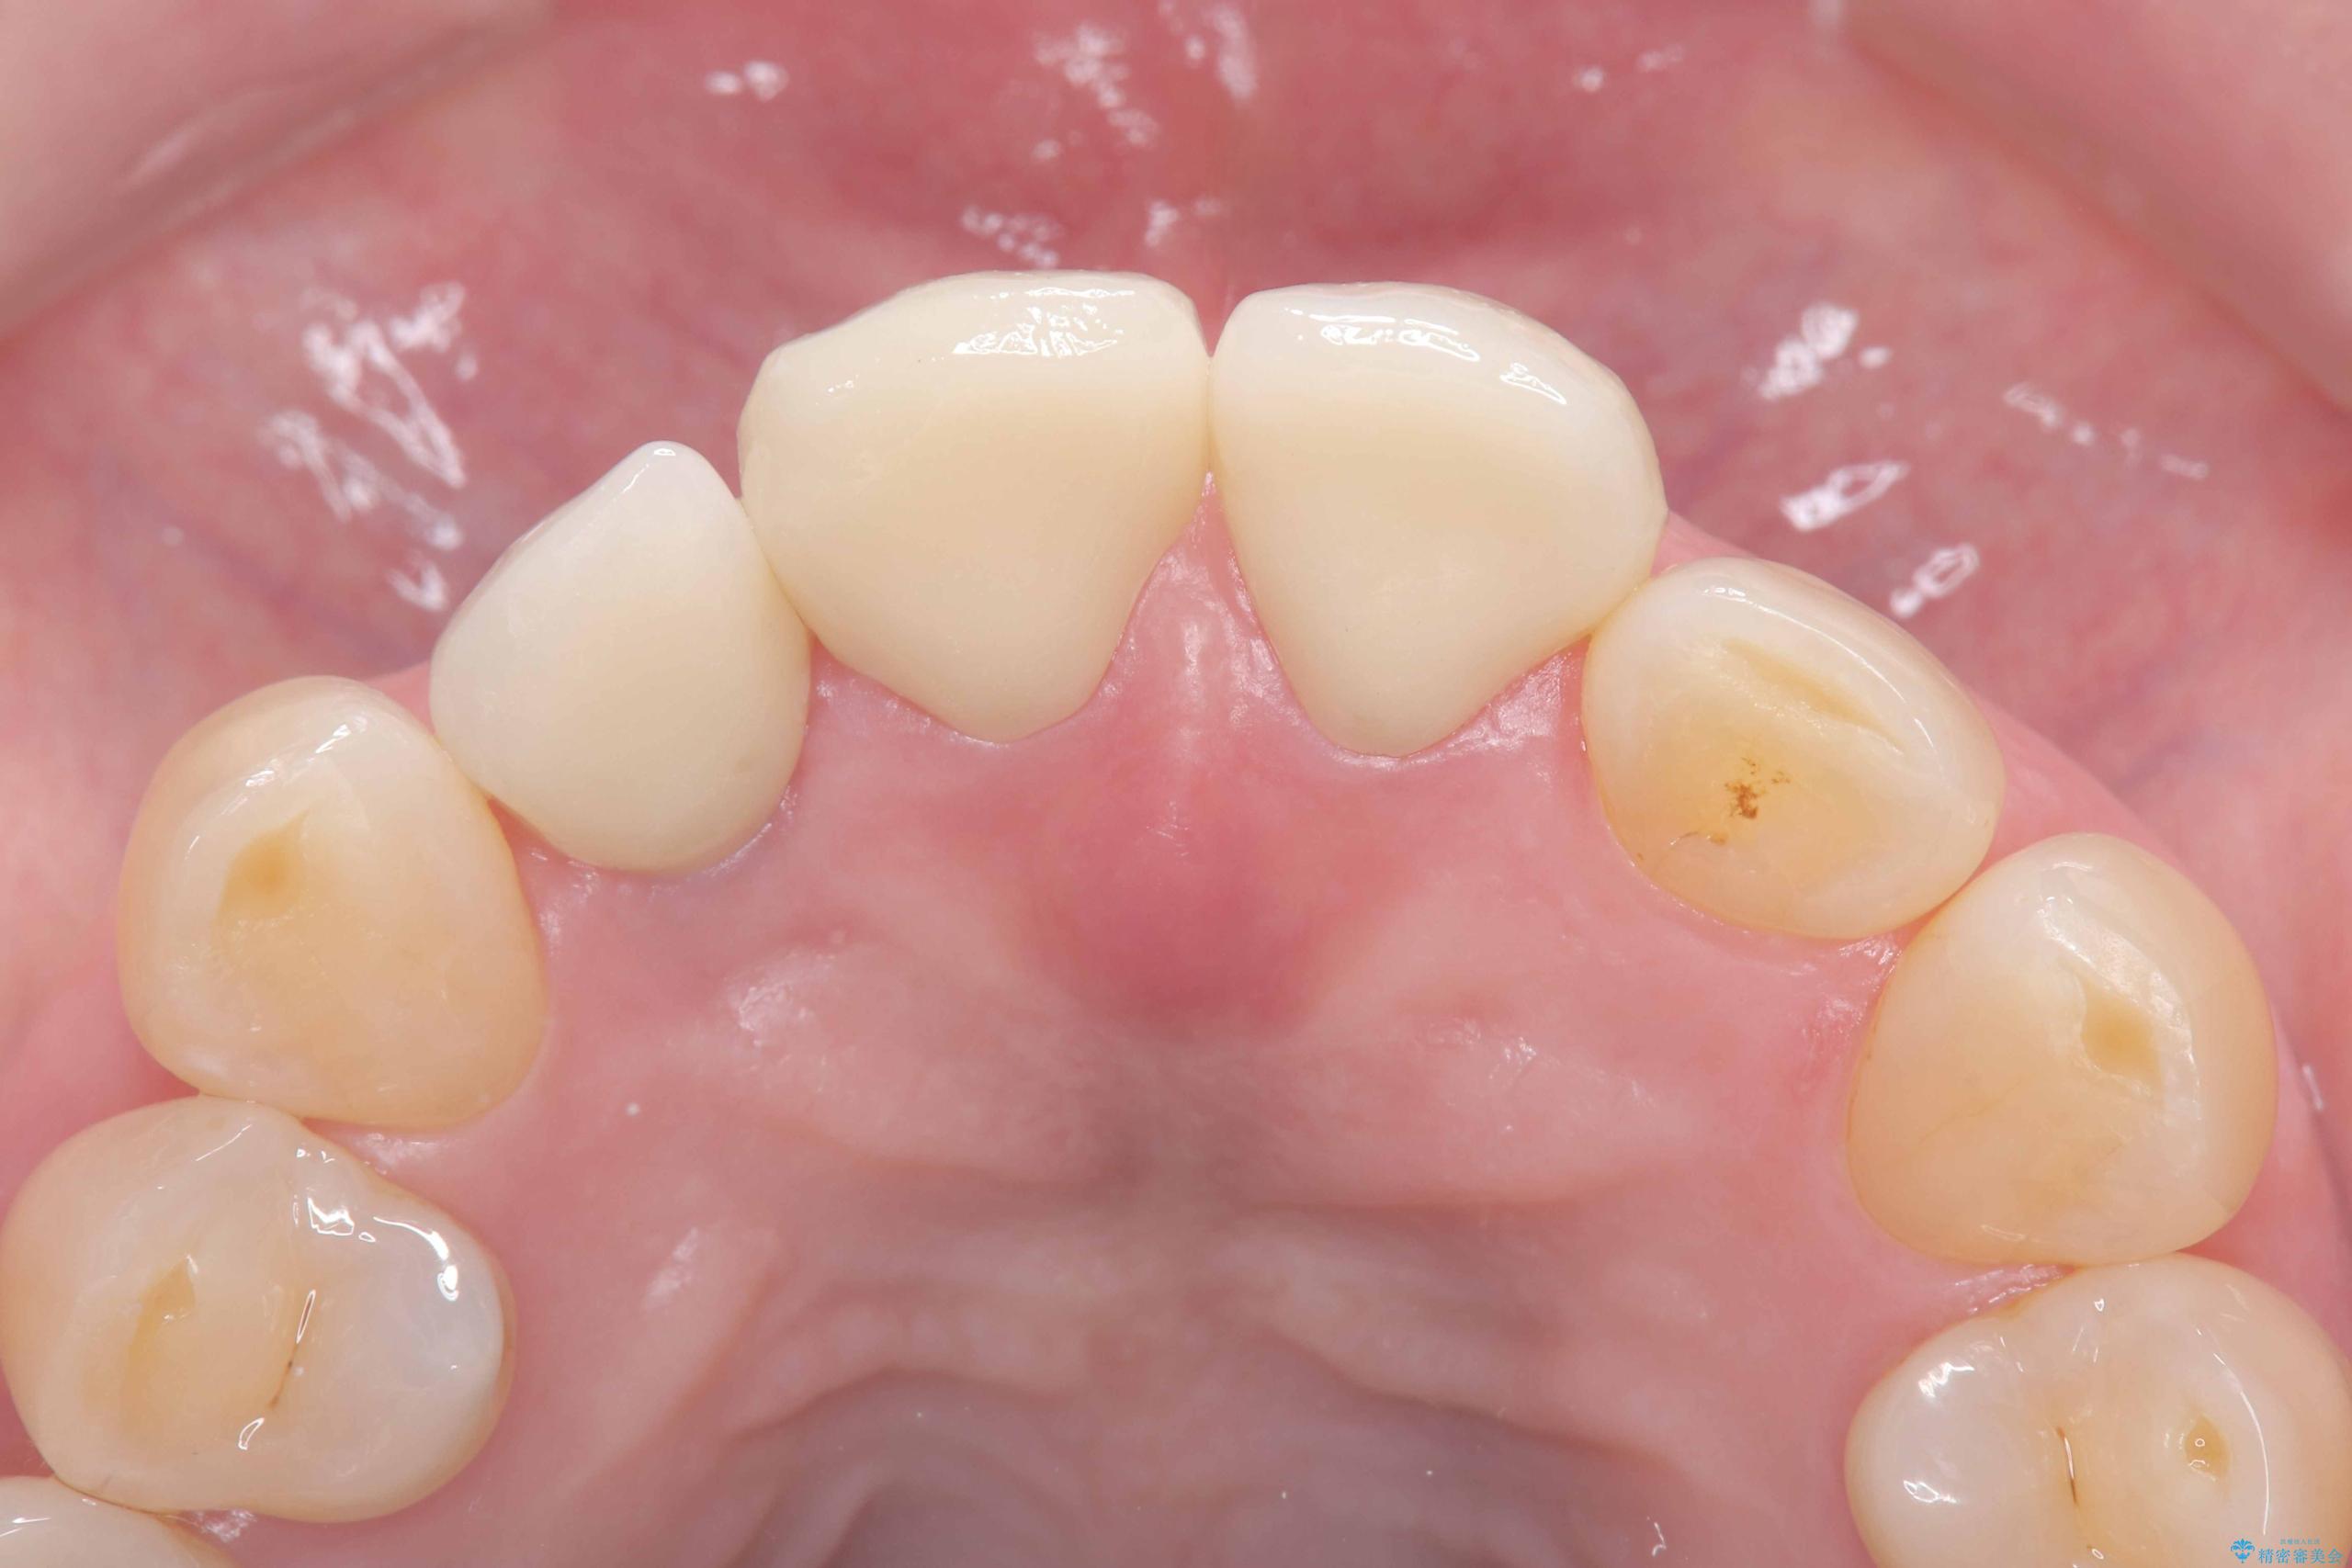

そのため今回は、右上2番を抜歯し、右上1番および左上1番をオールセラミッククラウンで審美的に修復しました。